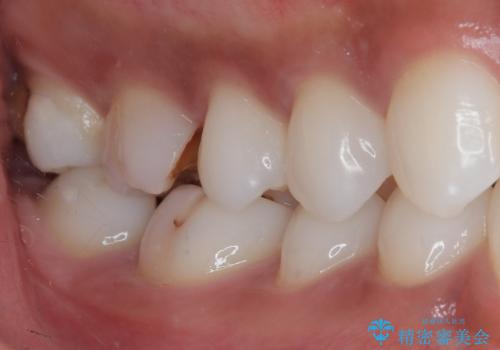

- 銀歯の詰め物が外れてしまったので、これを機にセラミックにやり替えたいと来院されれた患者様です。

精度の高い詰め物は二次的な齲蝕になりにくいです。